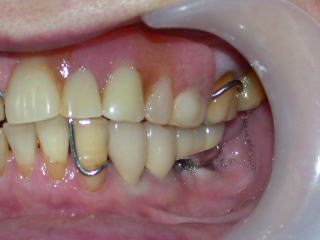

症例3

事前にインプラント植立する左側の咬合負担を軽くするために、上と右下の義歯の咬み合わせを高くしてあります。

歯肉の形状は、歯肉がコブ状で不整形ですが、いずれ平坦で滑らかな形状となります。

再び仮歯を付けてインプラントの固定を兼ねます。